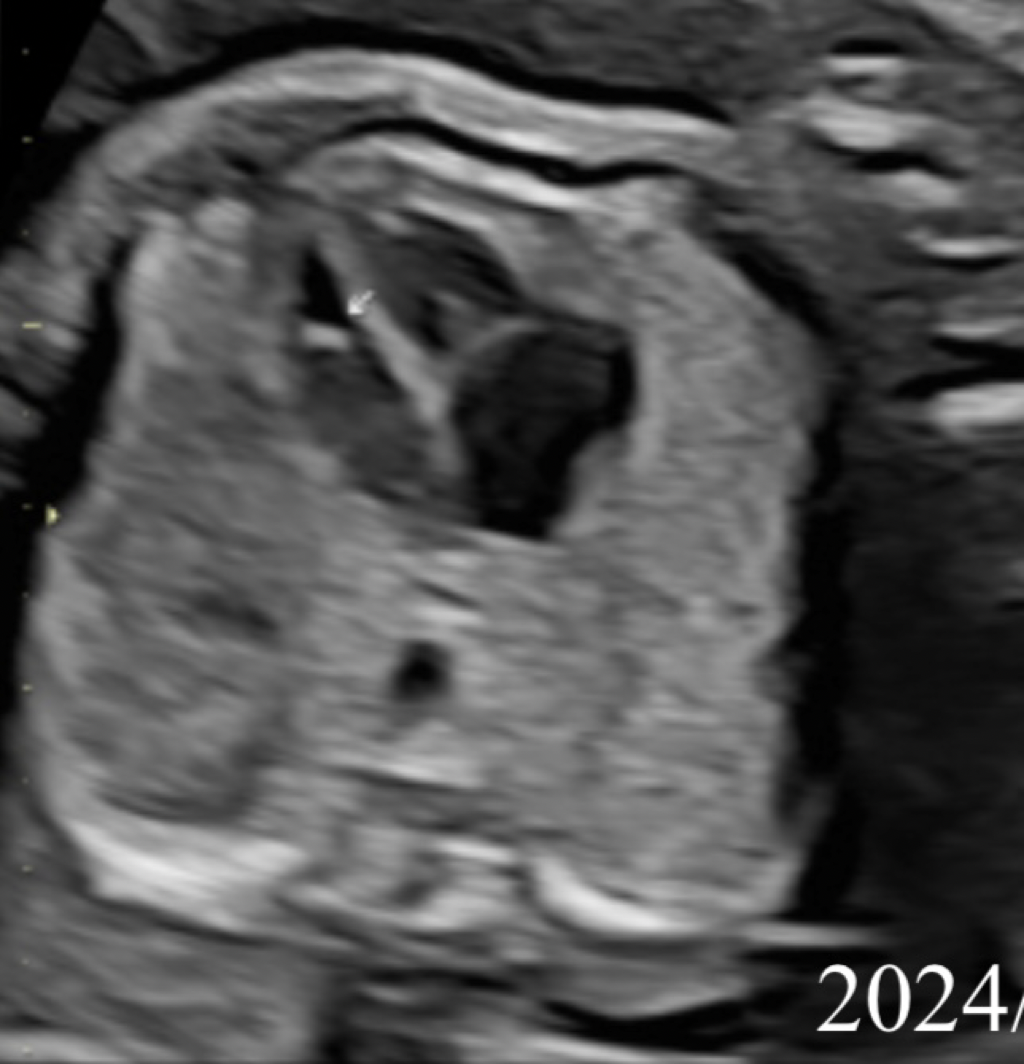

如題,上個禮拜去做高層次發現寶寶心臟有小白點及心室中膈缺損0.14cm

產檢醫師看到報告說這沒什麼問題,VSD後期會自動癒合叫我不用太擔心,可以繼續妊娠。